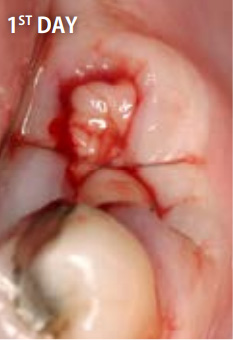

上記の写真はリッジプリザベーションにPRGFを用いたもので、非常に高い効果を得ることができます。

●PRGFを利用した場合

抜歯直後

抜歯してできた穴にPRGFを入れると、上皮や骨の再生が促進され、短期間で抜歯窩がふさがります。また、抜歯後の痛みと腫れも軽減します。

一方、自然治癒を待つ場合には、穴が完全にふさがるまでに数ヶ月かかります。その間にドライソケット(抜歯窩治療不全)になったり、食べ物が詰まるなど、痛みや悪臭を伴うこともあります。